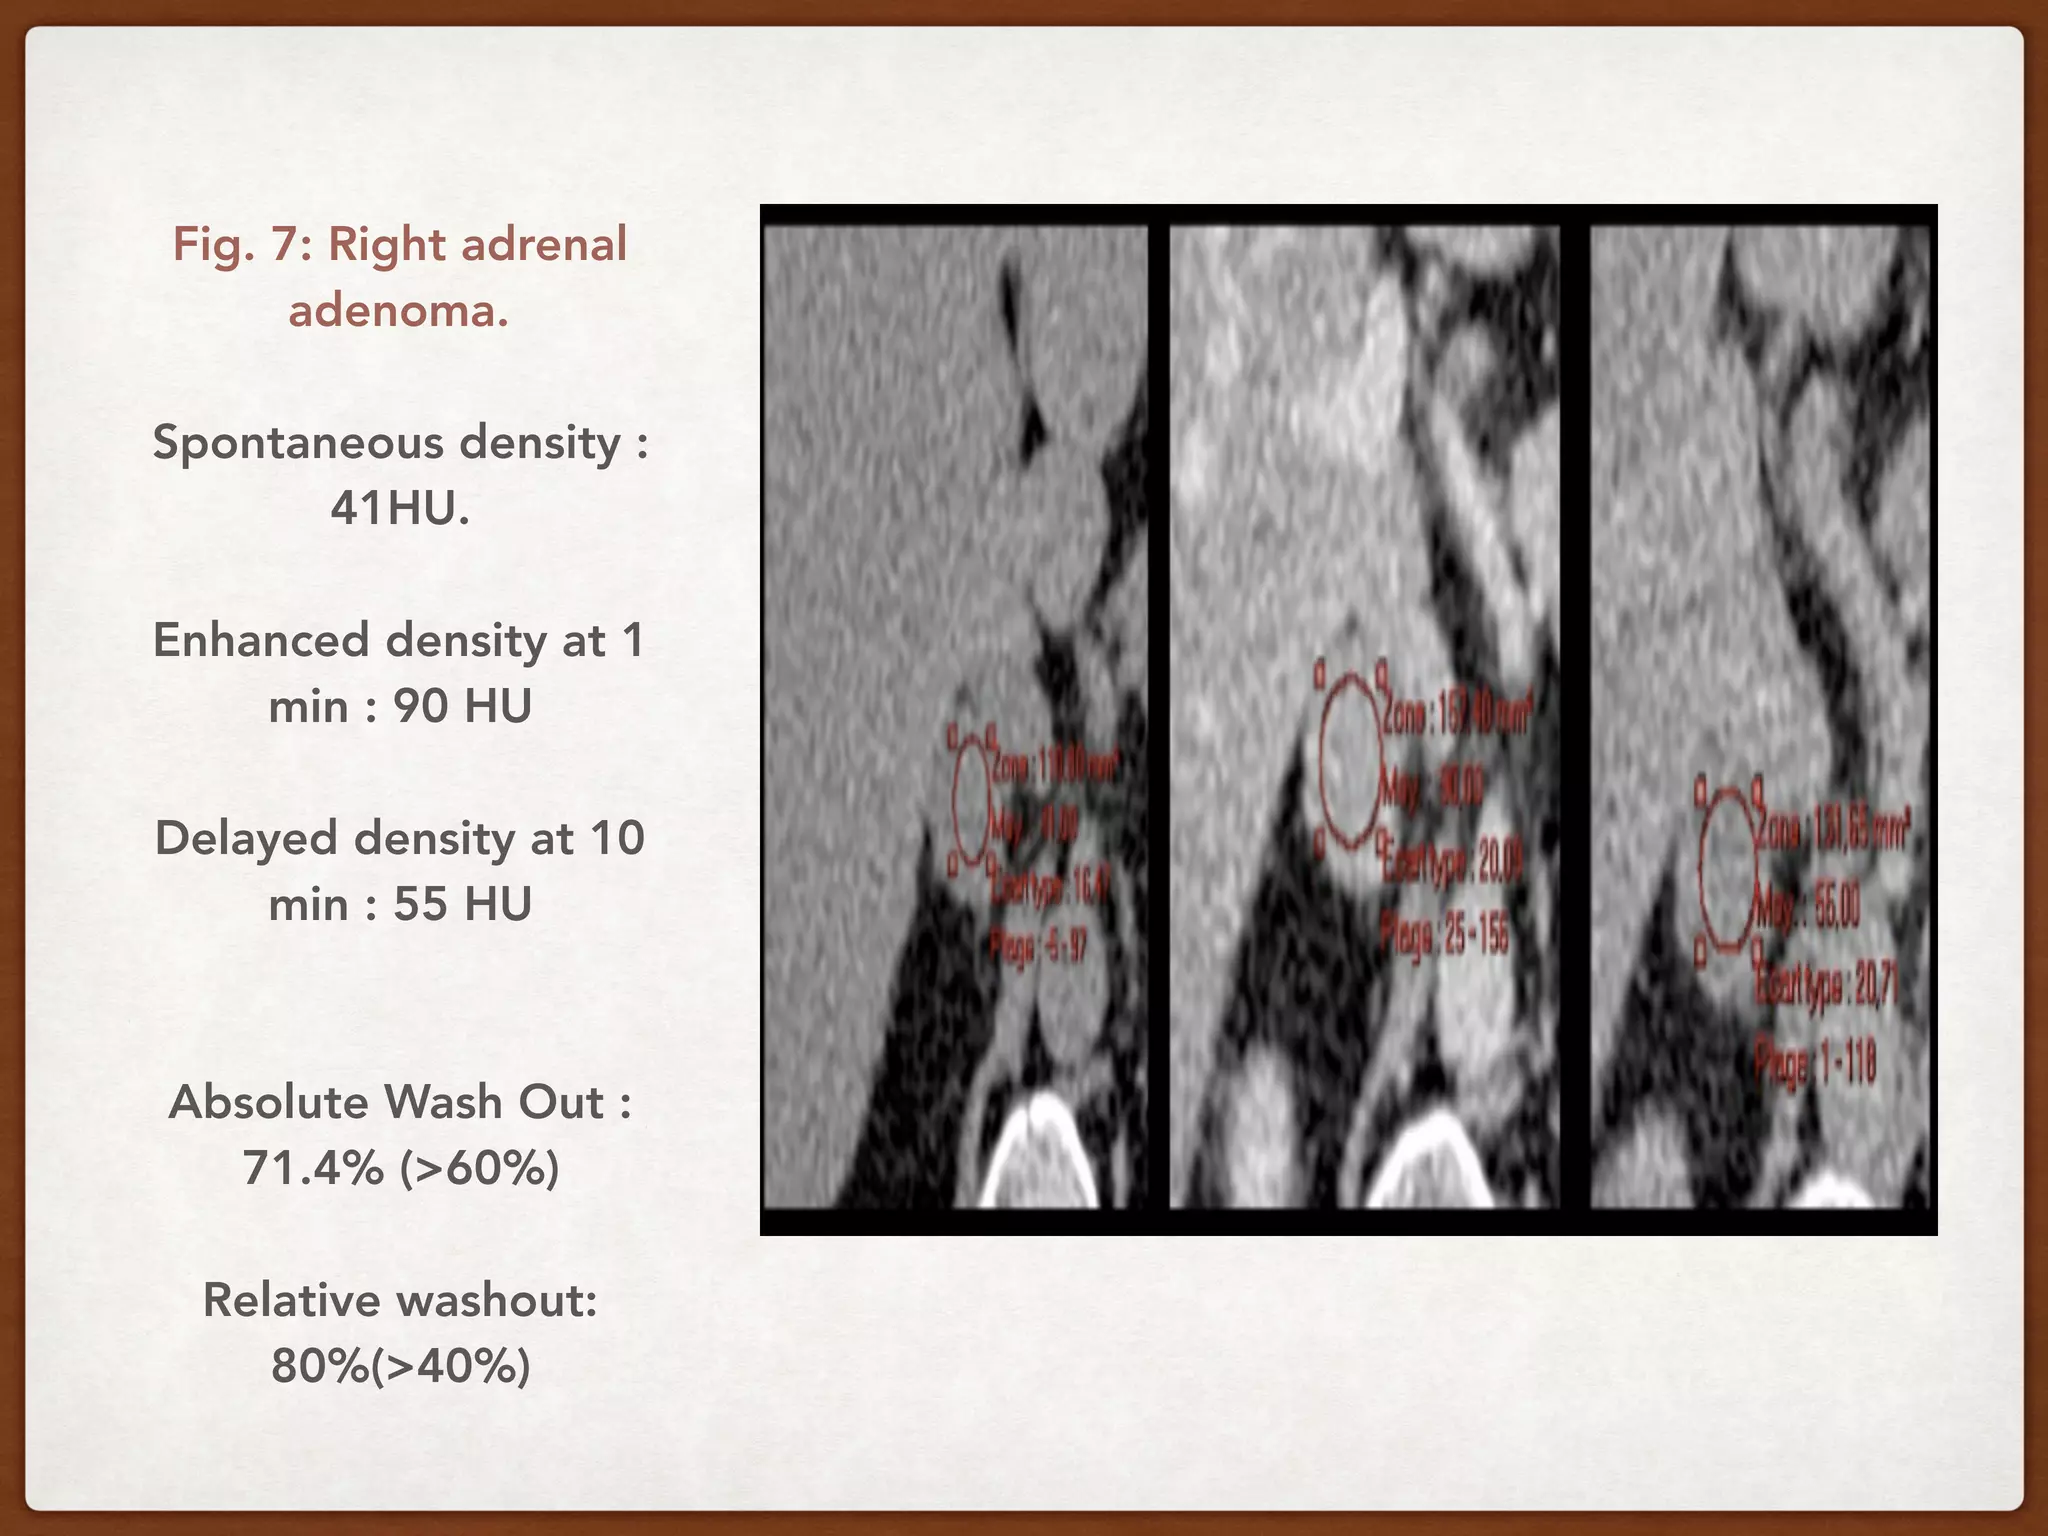

Fig. 7: Right adrenal

adenoma.

Spontaneous density :

41HU.

Enhanced density at 1

min : 90 HU

Delayed density at 10

min : 55 HU

Absolute Wash Out :

71.4% (>60%)

Relative washout:

80%(>40%)

Fig. 7: Rightadrenal adenoma. Spontaneous density : 41HU. Enhanced density at 1 min : 90 HU Delayed density at 10 min : 55 HU Absolute Wash Out : 71.4% (>60%) Relative washout: 80%(>40%)